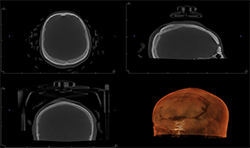

Case 2:66-year-old woman with edentulous maxillae

Two-dimensional imaging can’t evaluate the volume of the alveolar process accurately, especially in the buccolingual direction (Fig. 3)

CBCT imaging shows the volume of the alveolar process in any direction for implant treatment planning. (Figs. 4A, 4B) CBCT software allows one to measure the height and width of the alveolar ridge (Fig. 4C). This patient doesn’t have adequate bone volume for implant placement in the posterior left maxilla (Fig. 4D). Due to the severe alveolar ridge resorption, gaining adequate bone volume was recommended.

Fig. 3

Fig. 4A

Fig. 4B

Fig. 4C

Fig. 4D